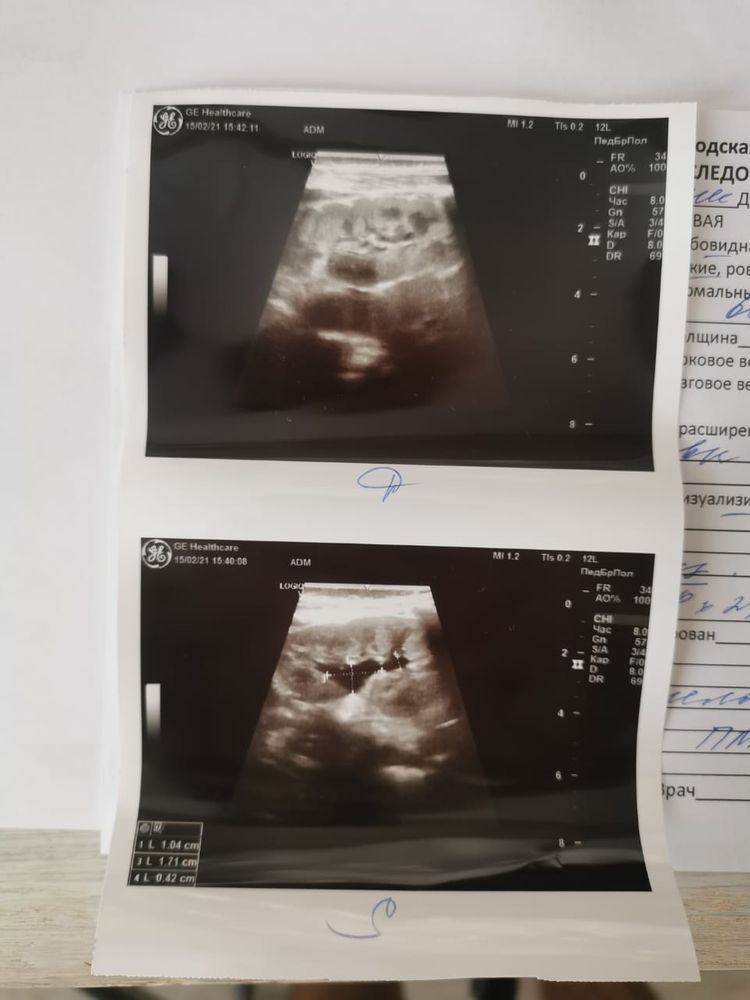

Здравствуйте, скажите есть ли что страшное на узи?

Аня Ягупова, простите, не всегда вижу здесь уведомления. УЗИ не ужасное, но есть причины не расслабляться. Непонятно, почему узист заподозрил ПМР. Вам бы обследование пройти: цистография, урография

Ещё странно написали: мочеточники не визуализируются. Не смотрели что ли?.. Их же, по сути, тоже нужно смотреть. Это важно для понинимания всей картины...